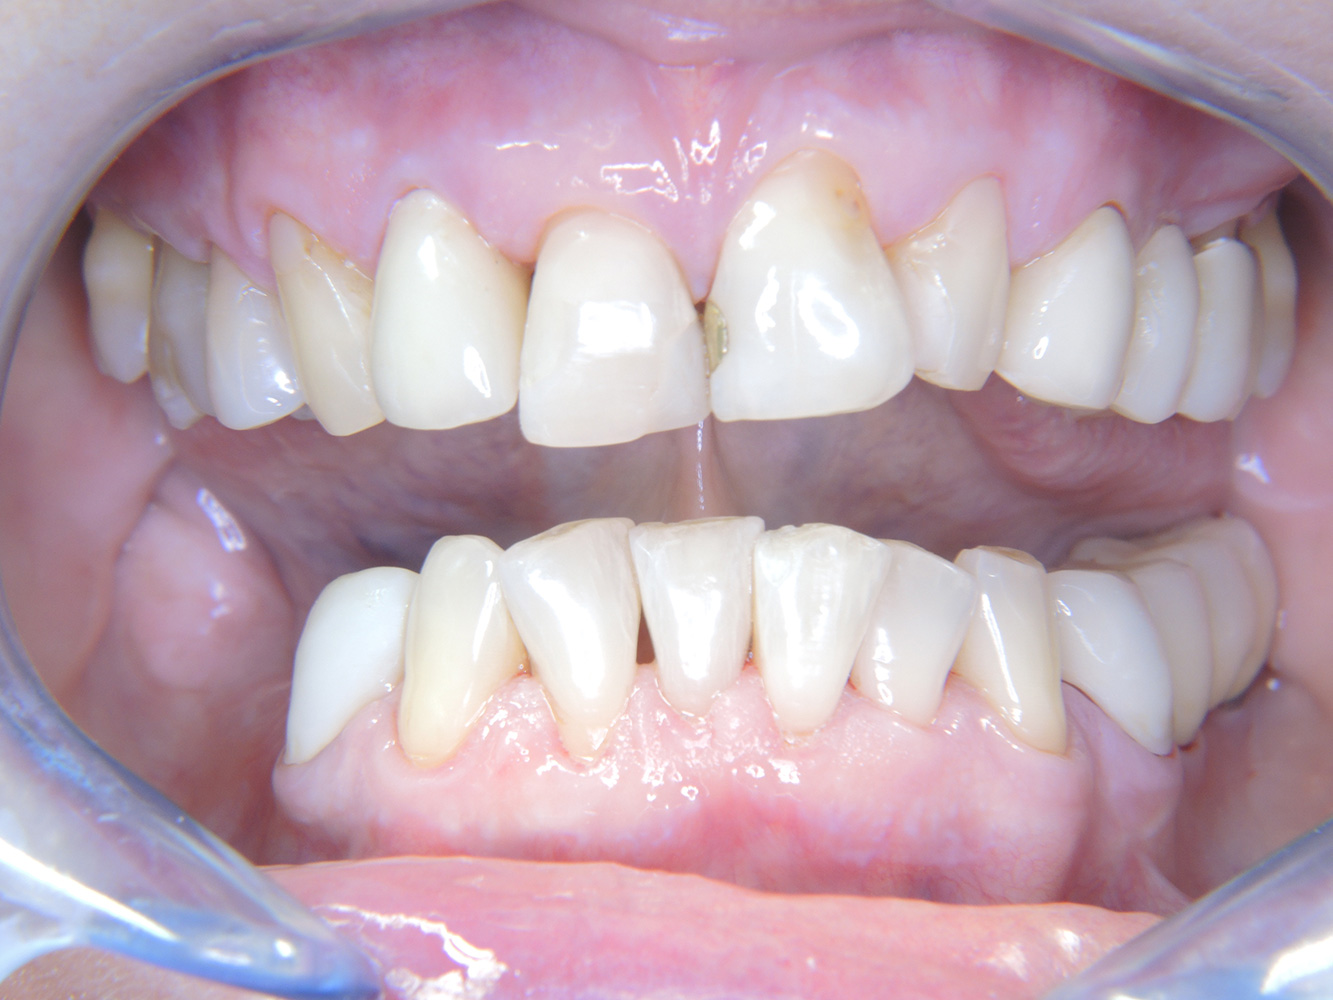

Die 68-jährige Patientin hat keine zahnmedizinisch relevanten allgemeingesundheitlichen Vorerkrankungen oder Medikation, auch aus dem Lebensstil ergibt sich kein besonderes Risiko. Die Patientin hat zwei Implantate (3. Quadrant, seit fünf Jahren) sowie eine parodontale Vorerkrankung (Parodontitis Stadium IV, Grad B) mit Zahnverlust. Derzeit zeigen sich stabile parodontale Verhältnisse. Für die Prophylaxesitzung ergeben sich vier Empfehlungen in den Bereichen Anamnese/Befund, Motivation/Instruktion, der Wahl der geeigneten Instrumente und für Resümee/Folgetermin.

Da die Patientin keine besonderen Risikofaktoren mit spezifischen zahnmedizinischen Auswirkungen hat, ist der aus der Mundgesundheit ermittelte Bedarf maßgebend. Hier ist einmal jährlich ein ausführlicher Parodontalstatus empfohlen. So kann rechtzeitig auf eine mögliche Progression der parodontalen Vorerkrankung oder die Entstehung einer Periimplantitis reagiert werden.

Trotz der stabilen Verhältnisse sollten auch bei dieser Patientin die Motivation/Instruktion nicht vernachlässigt werden. Besonderes Augenmerk gilt dem Erlernen der richtigen Implantatpflege. Gerade hier kann eine gute häusliche Pflege einen wichtigen Anteil an der langfristigen Stabilisierung der Mund- und Implantatgesundheit haben.

Aufgrund der Implantatsituation mit parodontaler Vorerkrankung hat die Patientin ein Entstehungsrisiko für eine Periimplantitis – empfohlen wird eine Wiedervorstellung im Intervall von drei bis vier Monaten.